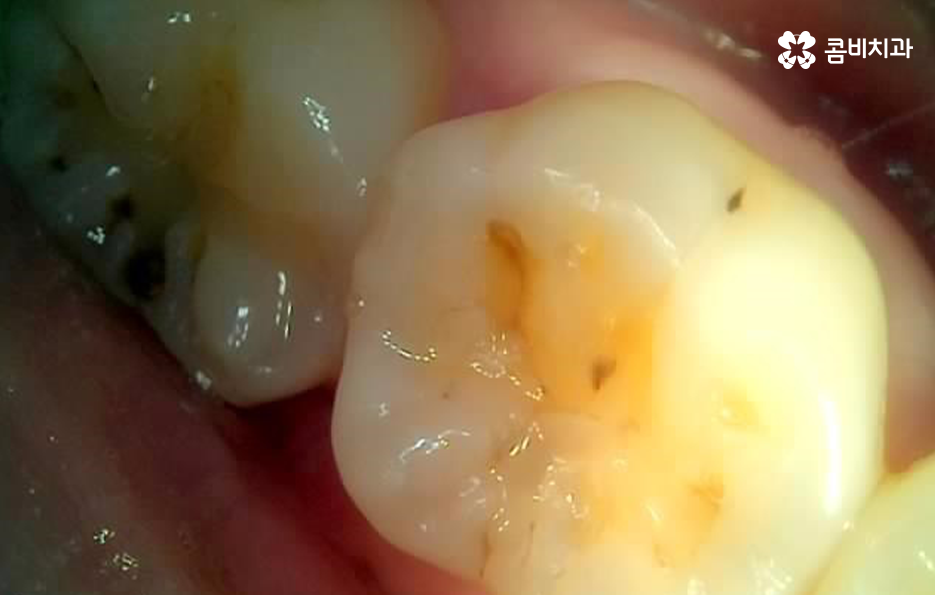

어금니 레진으로 치료 했던 부위의 주변에 검게 변색되었어요. 그리고 주변이 깨졌어요

어금니 초기 손상에 주로 활용되고 있는 어금니 레진 역시도 레진의 재료적 특성을 이해하고 적절한 재치료 시기가 되면 제때 교체를 하는 것이 치아 내부로 손상이 이어지는 것을 조금이라도 줄일 수 있는데요

어금니 레진 치료 후에 레진 자체가 깨지거나 주변 치아가 깨진 경우에는 당장 안아파도 치과에서 재치료를 받는 것이 추가적인 파절을 예방하고 치아 내부로 충치가 발생되는 것을 예방할 수 있으며 특히 주변이 검게 변색되는 경우에는 착색인 경우도 있지만, 2차 충치가 이미 진행된 경우가 많기 때문에 통증과는 무관하게 치과 방문을 권하고 있어요